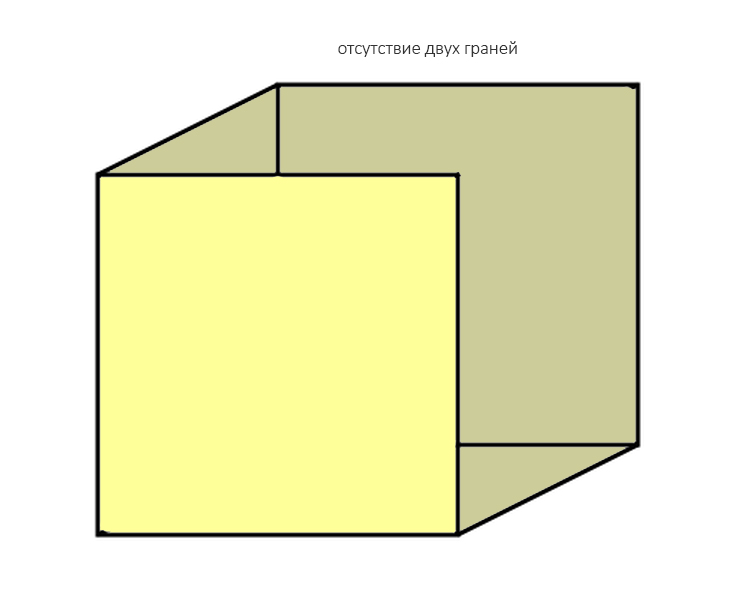

Отсутствие двух стенок — «классика жанра»:

к ней относятся большинство видов атрофии при длительном отсутствии зубов:

Ну и, отсутствие трех стенок характерно для значительных дефектов кости: